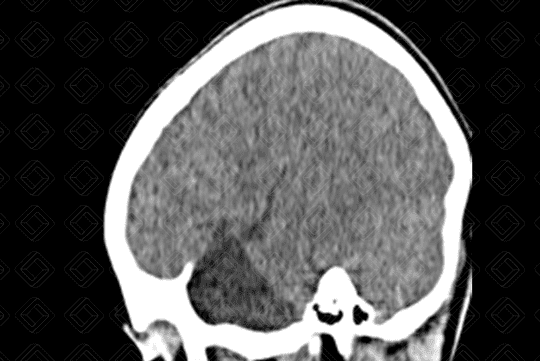

Descrição da lesão: Tomografia computadorizada do crânio. Lesão hipodensa, extra-axial, com densidade semelhante ao liquor, na fossa craniana média, deslocando o lobo temporal direito posteriormente (asterisco).

Cisto aracnoide: Caracteriza-se por uma expansão meníngea, em forma de bolsa, preenchida por líquido, com densidade semelhante ao liquor, mais comumente diagnosticada nas crianças e adultos jovens, sendo frequentemente um achado de imagem. Sua localização mais comum é na fossa craniana média (50-60% dos casos), mais especificamente na região temporal, adjacente à fissura sylviana. Outras localizações menos comuns são ângulo pontocerebelar e suprasselar (10% cada).

• Tomografia computadorizada do crânio: Lesão extra-axial, hipodensa, com densidade semelhante ao liquor e sem realce pelo meio de contraste. Pode ocorrer remodelamento ósseo da calota craniana adjacente à lesão, especialmente na população pediátrica;